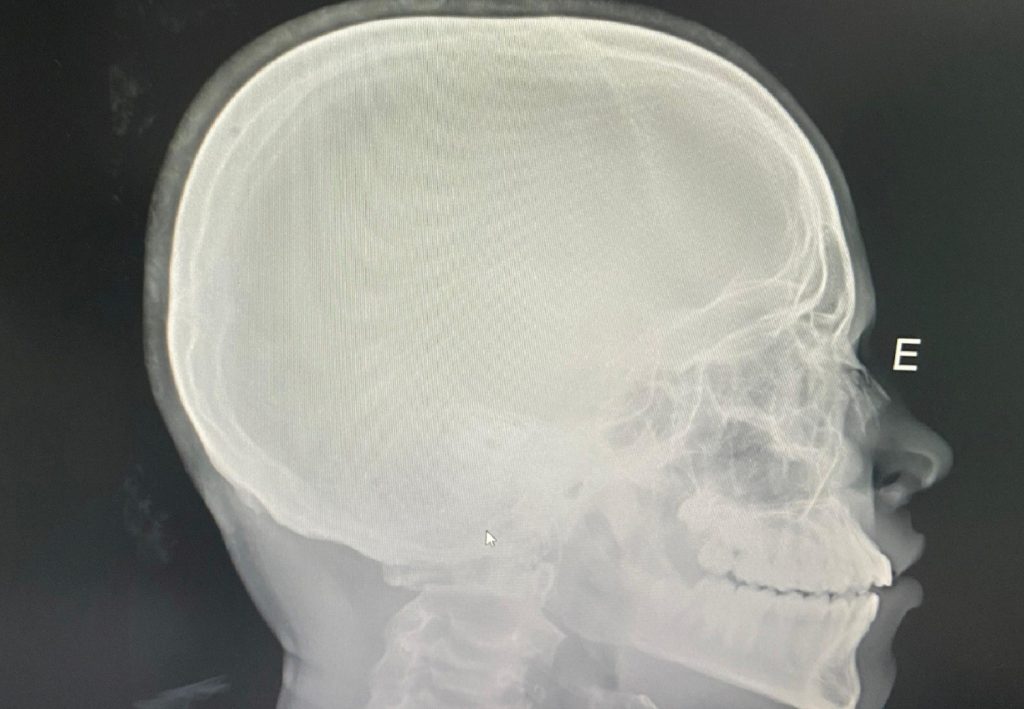

Estudante sofre fratura no nariz após levar soco de colega dentro de escola em Dianópolis

Um adolescente de 12 anos sofreu fratura no nariz após ser agredido por um colega dentro do Colégio Estadual João D’Abreu, em Dianópolis, na região sul do Tocantins. Segundo a família, o estudante era alvo de ofensas racistas e bullying há cerca de um ano.

Estudante fraturou o nariz após ser agredido com um soco

Arquivo Pessoal/Vinicius Moraes